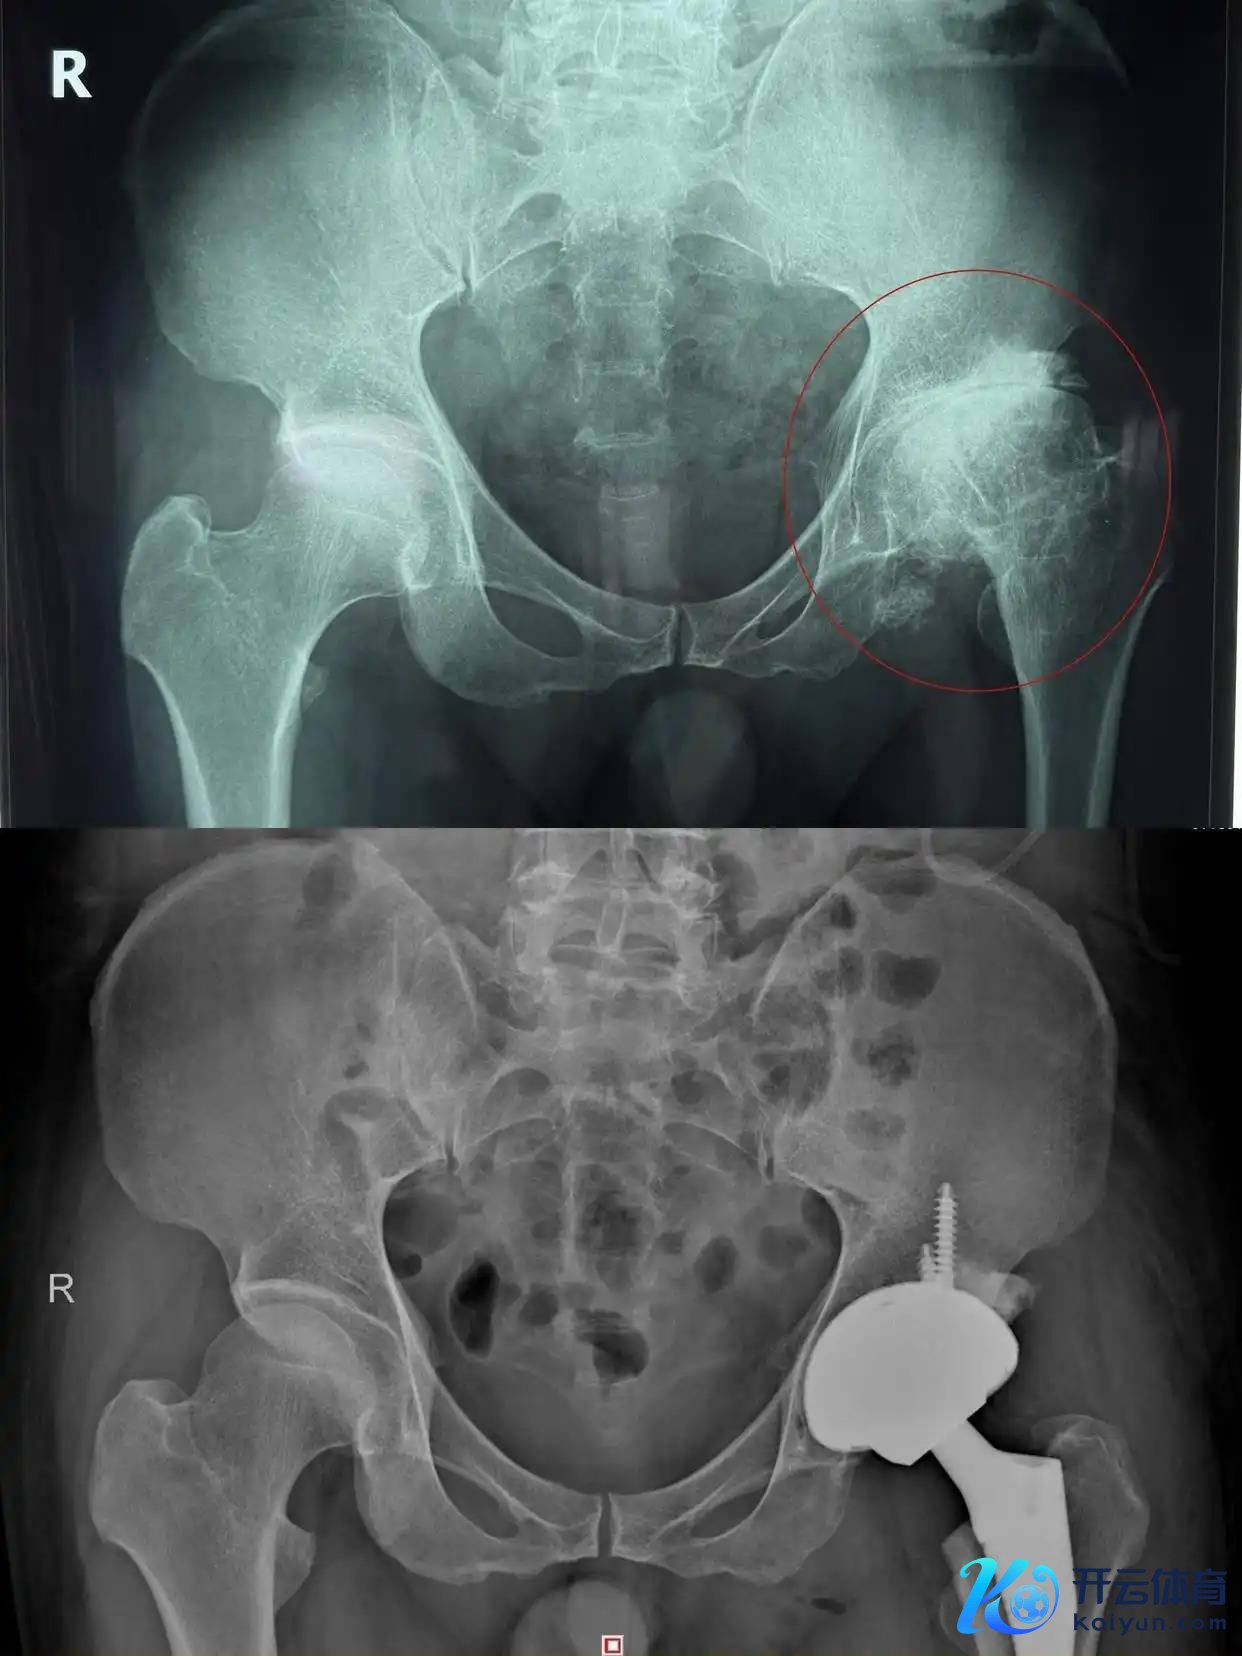

家住益阳的52岁杨先生左髋部反复疾苦20余年,近期疾苦加重、要害步履严重受限体育游戏app平台,就医确诊为股骨头坏死晚期,近日在湖南省第二东说念主民病院骨要害畅通医学科,继承全髋要害置换手术才得以缓解,当今正在进一步康复中。医师教唆,弥远激素使用是股骨头坏死的高危身分,早识别、早干扰至关遑急。

第三,晚期(塌陷严重、疾苦剧烈):全髋要害置换术是当今最锻真金不怕火、后果最信得过的调养神志,术后可快速规复行走与普遍步履,生存质地显耀进步。